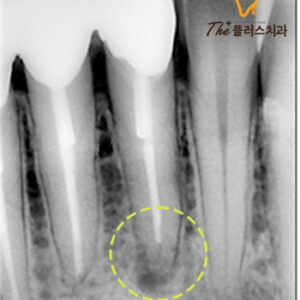

22. 울산남구치과 브릿지에 구멍이 났어요.

울산남구치과 브릿지에 구멍이 났어요.   안녕하세요. 모든 진료에 진심을 다하는 곳, 더플러스치과입니다.   치아를 잃게 되었을 때 이를 대체할 수 있는 방법으로는 임플란트나 브릿지, 틀니 등 다양한 방법이 있습니다.   그중에서도 브릿지는 상실된 치아의 인접한 치아를 삭제한 후 지대치로 사용하여 더보기…